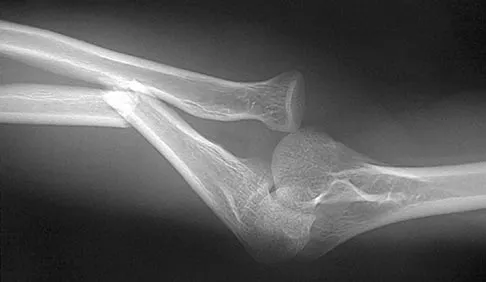

Figure 38 shows the radiograph of a 16-year-old wrestler who injured his elbow when he was thrown to the mat by his opponent. To minimize additional trauma to the medial soft tissues, the elbow should be reduced in

Explanation